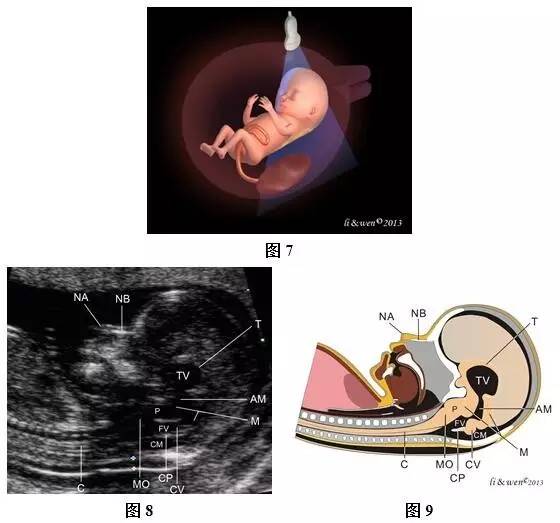

(三)胎儿鼻骨 超声扫查方法:声束平面尽可能与鼻骨长轴相垂直,其他要求与NT测量切面相同,获取有一定倾斜角度(在300以内)的头颈上胸部正中矢状切面(图7~9)。

标准切面判断标准:此切面观察到鼻根、鼻尖及鼻骨呈3条强回声线,位于上方的线为皮肤强回声线,下方较粗且回声较上面皮肤明显增强者为鼻骨回声,第3条线与皮肤几乎相连但略高一点,则为鼻尖形成的短线。其他标准与NT切面相同

主要观察的内容及测量要求:主要观察鼻骨是否存在,怀疑鼻骨短小时,应测量鼻骨强回声线两端点之间的距离(即鼻骨长)。鼻骨显示不清时,应注意声束入射角是否得当,避免因声束入射角度不当误诊为鼻骨缺如或发育不良,此时应调整声束角度或加扫鼻骨横切面及冠状切面进一步确认鼻骨情况。

注:NB为鼻骨;NA为鼻尖;Di为间脑;Af为菱脑

图7~9孕13周胎儿鼻骨扫查模式图及声像图。图7胎儿鼻骨扫查模式图;图8、9胎儿鼻骨声像图及模式图